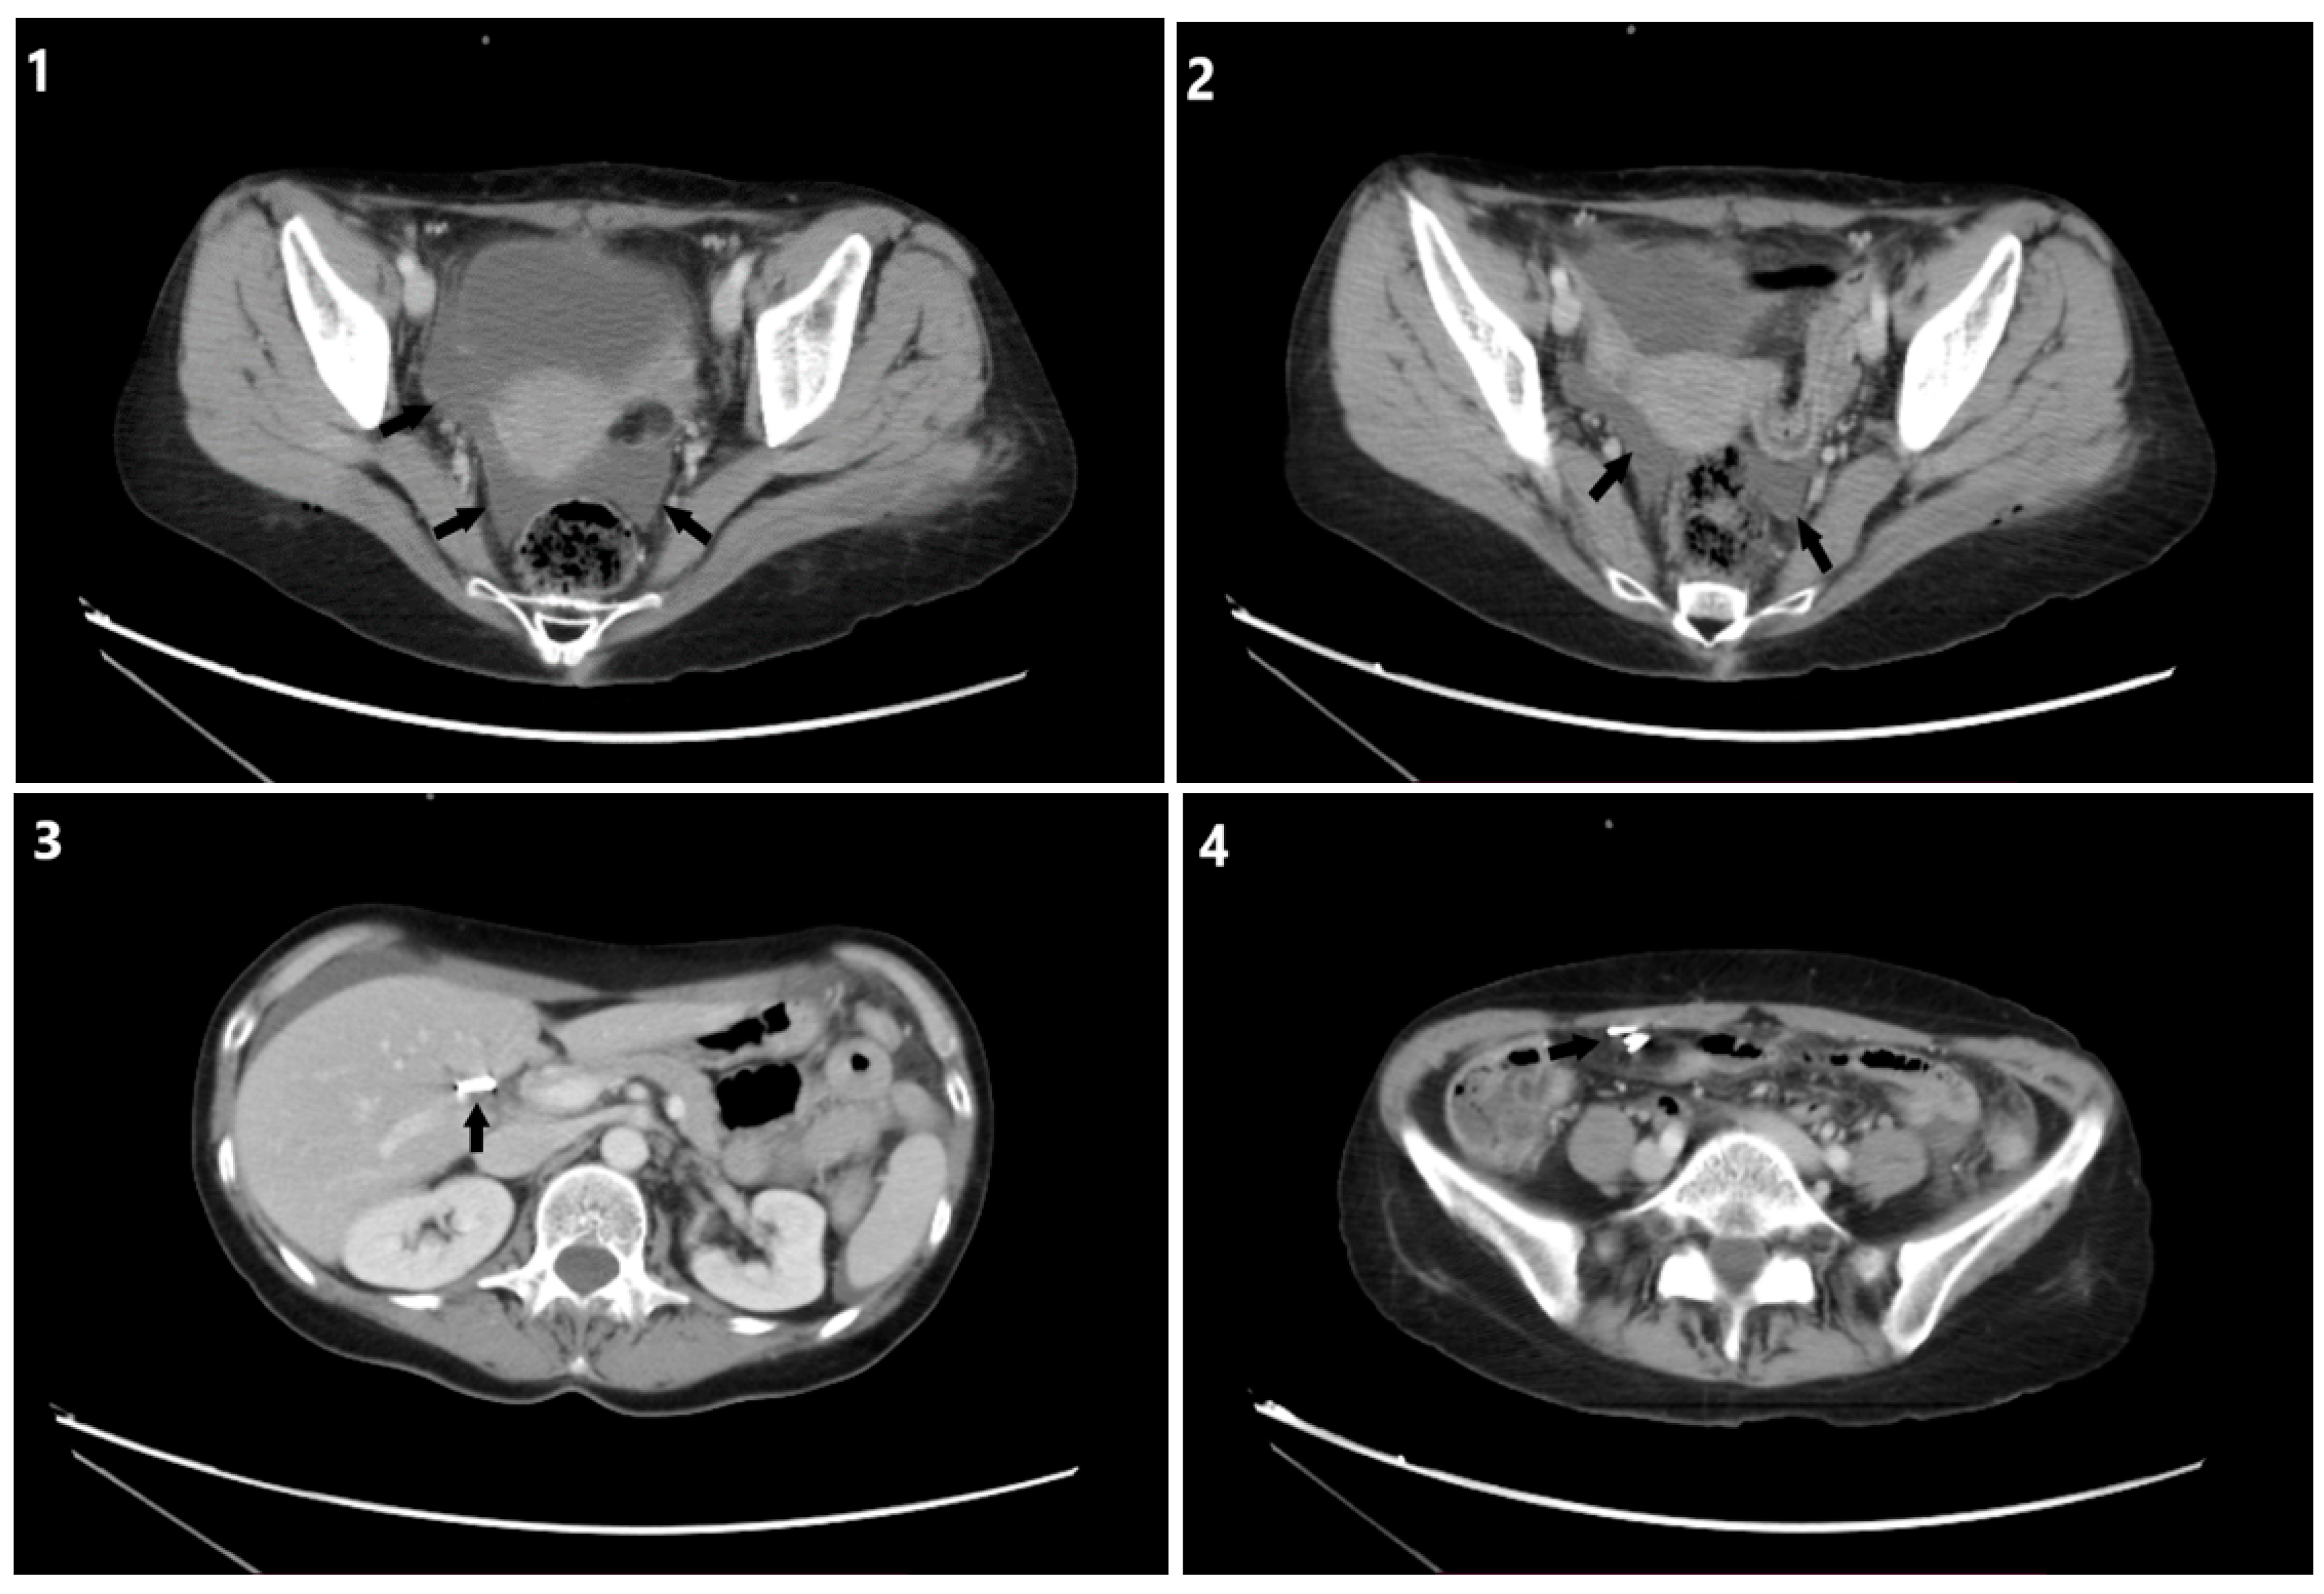

2. Case Description